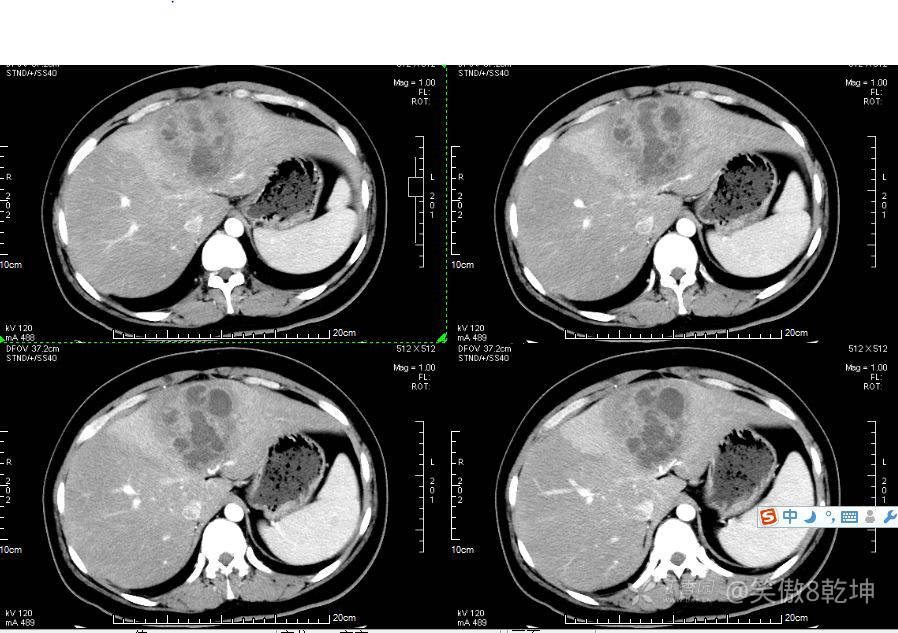

诊断似乎倾向于肝脓肿了,与患者或家属沟通后完善上腹部强化CT:

证实为肝脓肿,至此,诊断思路似乎清晰起来,患者血糖的升高使得微小血管容易出现循环障碍,同时白细胞的吞噬能力及抗感染能力下降,所有易出现感染性疾病。而肝脓肿通常不容易早期发现。患者的年龄同时让临床医生不容易想到此诊断。